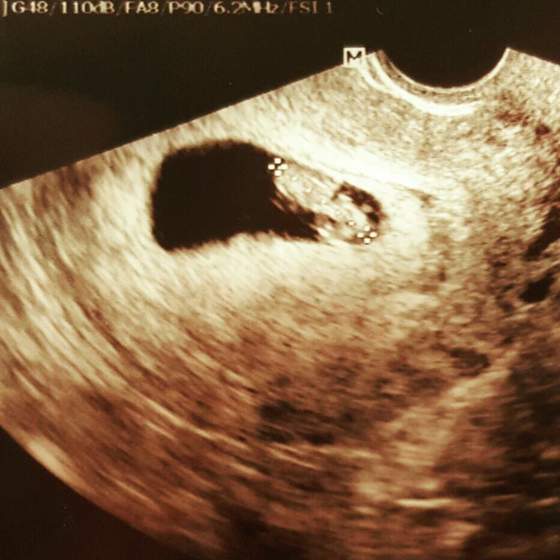

Oby tak dalej. Gratuluję :-)